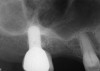

The 13-month postoperative radiograph. Significant regeneration is suggested.

Figure 20

In a case with an intrabony defect, such as with the patient in Figure 17, a periodontist might suggest sacrificing supporting bone to remove the osseous defect. Doing this might lead to issues related to tooth mobility, esthetics, caries, and hypersensitivity.

The patient had been referred for an implant consultation for the mandibular right canine. She had very deep probing depths on the lingual. When the flap was raised, a significant amount of subgingival calculus was seen as a local risk factor (Figure 18). However, she had no significant pathology to remove from the situation. Debridement was performed the same as in Case 3 with the rotary ultrasonic and manual instrumentation.

The defect was obturated with mineralized freeze-dried bone and hydrated with platelet-derived growth factor. As with any growth factor, when implementing it clinically, all growth factors require a carrier to bring that growth factor to the desired site, which do not elicit an inflammatory response. In this situation, it is the mineralized freeze-dried bone allograft. This combination was demonstrated by Rosen et al8 to be efficacious in treating intrabony defects. A biologic approach was taken both in terms of the graft and membrane (Figure 19). Primary closure was achieved.

At the 13-month postoperative visit, the patient who had initially been referred for extraction and an implant still has the tooth with minimal probing depths and no mobility (Figure 20). She reported that she is happy that she did not have to have her canine extracted.